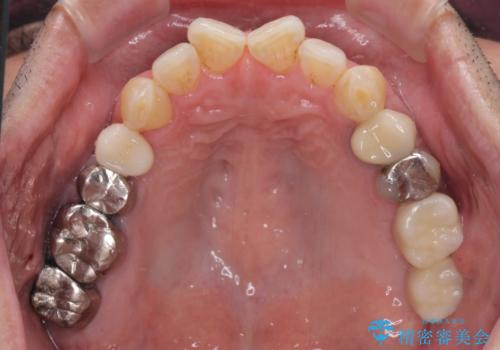

- 神経を抜く処置の後に装着した詰め物が外れてしまったとのことで来院された患者様です。

患者様自身、当院の症例をご覧になり、神経の取り除かれた歯はクラウンを装着するべきと理解していただいていたため、詰め物の捕れた歯とその後ろの歯の2本を補綴治療することとしました。